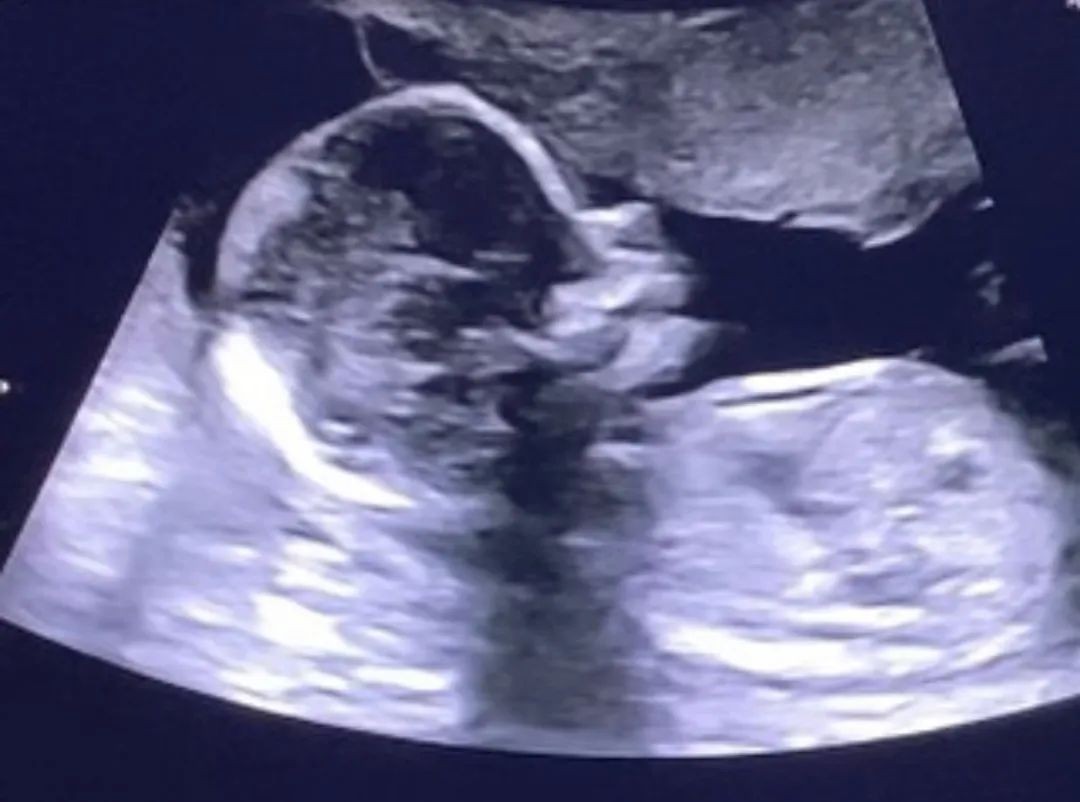

而且陈泰贤还将ins头像改为了胎儿B超的黑白照,同时个性签名中的“死产”一词也非常引人注目,可以感受到他的内心十分难受。